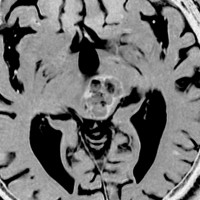

左上のT2*でみられるように多発性海綿状血管腫の成人男性に発生した中脳海綿状血管腫です。複視と歩行失調で発症して,数回の脳幹部出血を繰り返し,水頭症になったために第3脳室開窓術がなされました。それでも出血は止まらず、両側の動眼神経麻痺による両側眼瞼下垂,歩行失調,嚥下障害などさまざまな中脳症状が進行しました。

しかたがないので手術で摘出しました。なんとか眼瞼が持ち上がるようになり歩行も可能で嚥下もできます。幸いだったのは感覚路(脊髄視床路)の障害による体性疼痛が生じなかったことです。

手術は経テント法 OTA という手法でした(クリックと手技が書いてあります)

片方の下丘の損傷だけでは神経脱落症状が出ないので,中脳内部の腫瘍を摘出するには下丘という狭い場所を切開して入りますが,この患者さんは左上丘も出血のために破壊されていて,間口が広かったといえます。でもこの手術は難しすぎるので決して積極的にはしません。